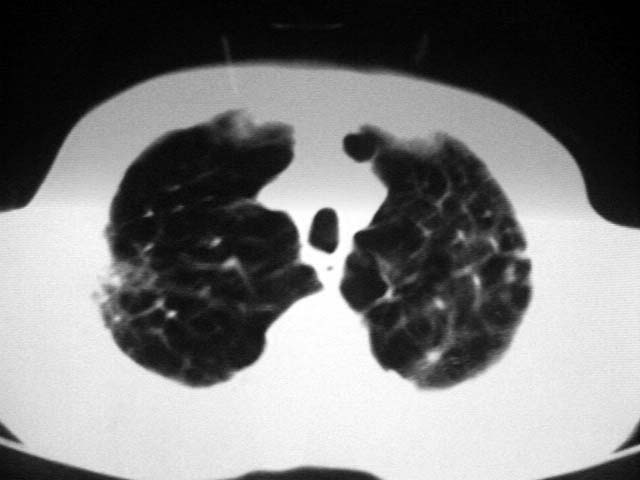

以下是引用zjzjr在2007-9-4 17:00:00的发言:[br]双上肺继发型结核伴左上肺空洞形成.慢性支气管炎伴肺气肿.

以下是引用liuzheng_9326在2007-9-4 16:23:00的发言:[br]痰检未见结核菌, 治疗后症状好转。图像符合陈旧性结核伴感染。